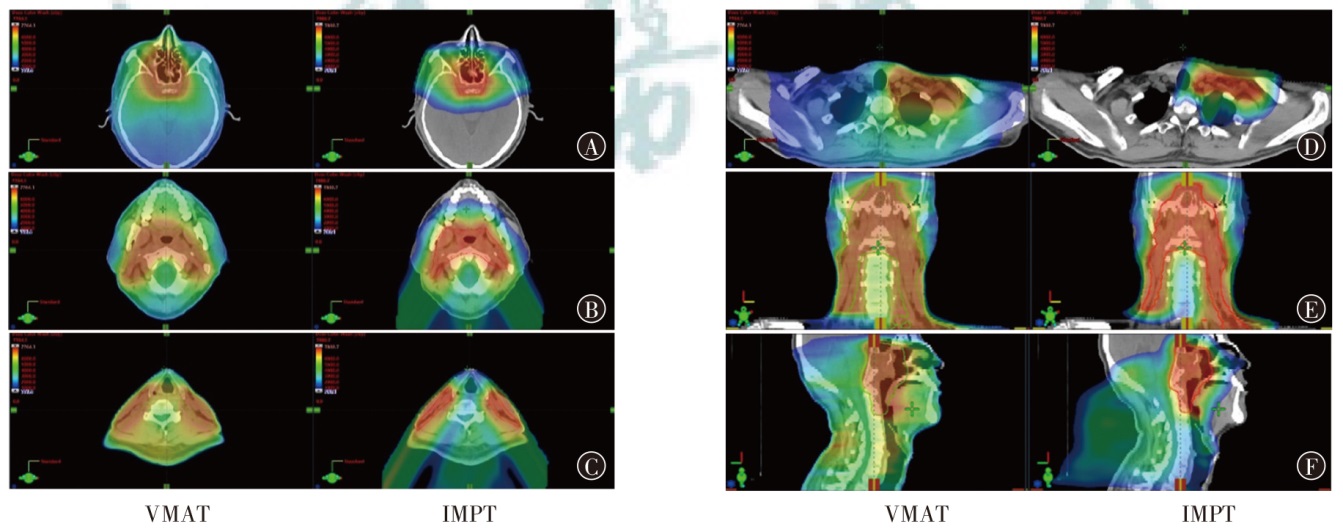

Objective To investigate the dosimetric characteristics of intensity modulated proton therapy (IMPT) and photon volumetric modulated arc therapy (VMAT) in typical head and neck malignant tumors. Methods Three types of typical head and neck tumors (nasopharyngeal carcinoma, parotid gland carcinoma, laryngeal carcinoma) treated at Shandong Cancer Hospital and Institute from December 2023 to December 2024 were taken as research subjects. IMPT and VMAT radiotherapy plans were created according to clinical prescription requirements of target and organs at risk limits respectively. The conformity index (CI), homogeneity index (HI) and gradient index (GI) for target coverage of two radiotherapy plans were evaluated for 3 patients, as well as the dosimetric indicators of organs at risk. Results The CI of IMPT for nasopharyngeal carcinoma, parotid gland carcinoma and laryngeal carcinoma were 0.70, 0.72 and 0.67, respectively. The HI were 0.11, 0.08 and 0.08, respectively. The GI were 3.08, 2.49 and 3.75, respectively. The CI of VMAT plans were 0.77, 0.82 and 0.91, respectively. The HI were 0.12, 0.10 and 0.04, respectively. The GI were 3.67, 2.63 and 3.45, respectively. The results showed that CI of IMPT plan was slightly lower than that of VMAT plan, and HI of IMPT plan was comparable to that of VMAT plan, the GI of the IMPT plan for patients with nasopharyngeal carcinoma and parotid gland carcinoma was lower than that of the VMAT plan, and the GI of the IMPT plan for patient with laryngeal carcinoma was higher than that of the VMAT plan, and all were within the clinically acceptable range. The IMPT plan has demonstrated significant dose advantages in the treatment of nasopharyngeal carcinoma, parotid gland carcinoma and laryngeal carcinoma. For patient with nasopharyngeal carcinoma, the IMPT plan reduced the Dmax of the left and right crystals by 54.1% and 50.4%, respectively, compared to VMAT plan, and reduced the Dmean of the oral and laryngeal tissues by 40.5% and 49.6%, respectively. For patient with parotid gland carcinoma, IMPT plan reduced the Dmax of the brainstem and spinal cord by 66.2% and 40.5%, respectively, compared to VMAT plan. For patient with laryngeal carcinoma, IMPT reduced spinal cord Dmax by 77.0%, while thyroid cartilage Dmean increased by 8.0% compared to VMAT plan. For the additional dose in the patients' body, taking the absolute volumes occupied by the prescribed dose areas of 10%, 30%, and 50% in the patients' body as examples, IMPT plan of nasopharyngeal carcinoma patient decreased by 29.7%, 29.6%, and 34.9% compared to VMAT plan, respectively. IMPT plan of parotid gland carcinoma patient decreased by 61.0%, 39.7%, and 17.4% compared to VMAT plan, respectively. IMPT plan of laryngeal carcinoma patient decreased by 63.9%, 31.7%, and 4.1% compared to VMAT plan, respectively. Conclusions Compared with VMAT plan, IMPT plan can effectively reduce the irradiation dose of most organs at risk near the target of head and neck tumors, but the dose of string organs close to the target area may be higher, which needs attention.